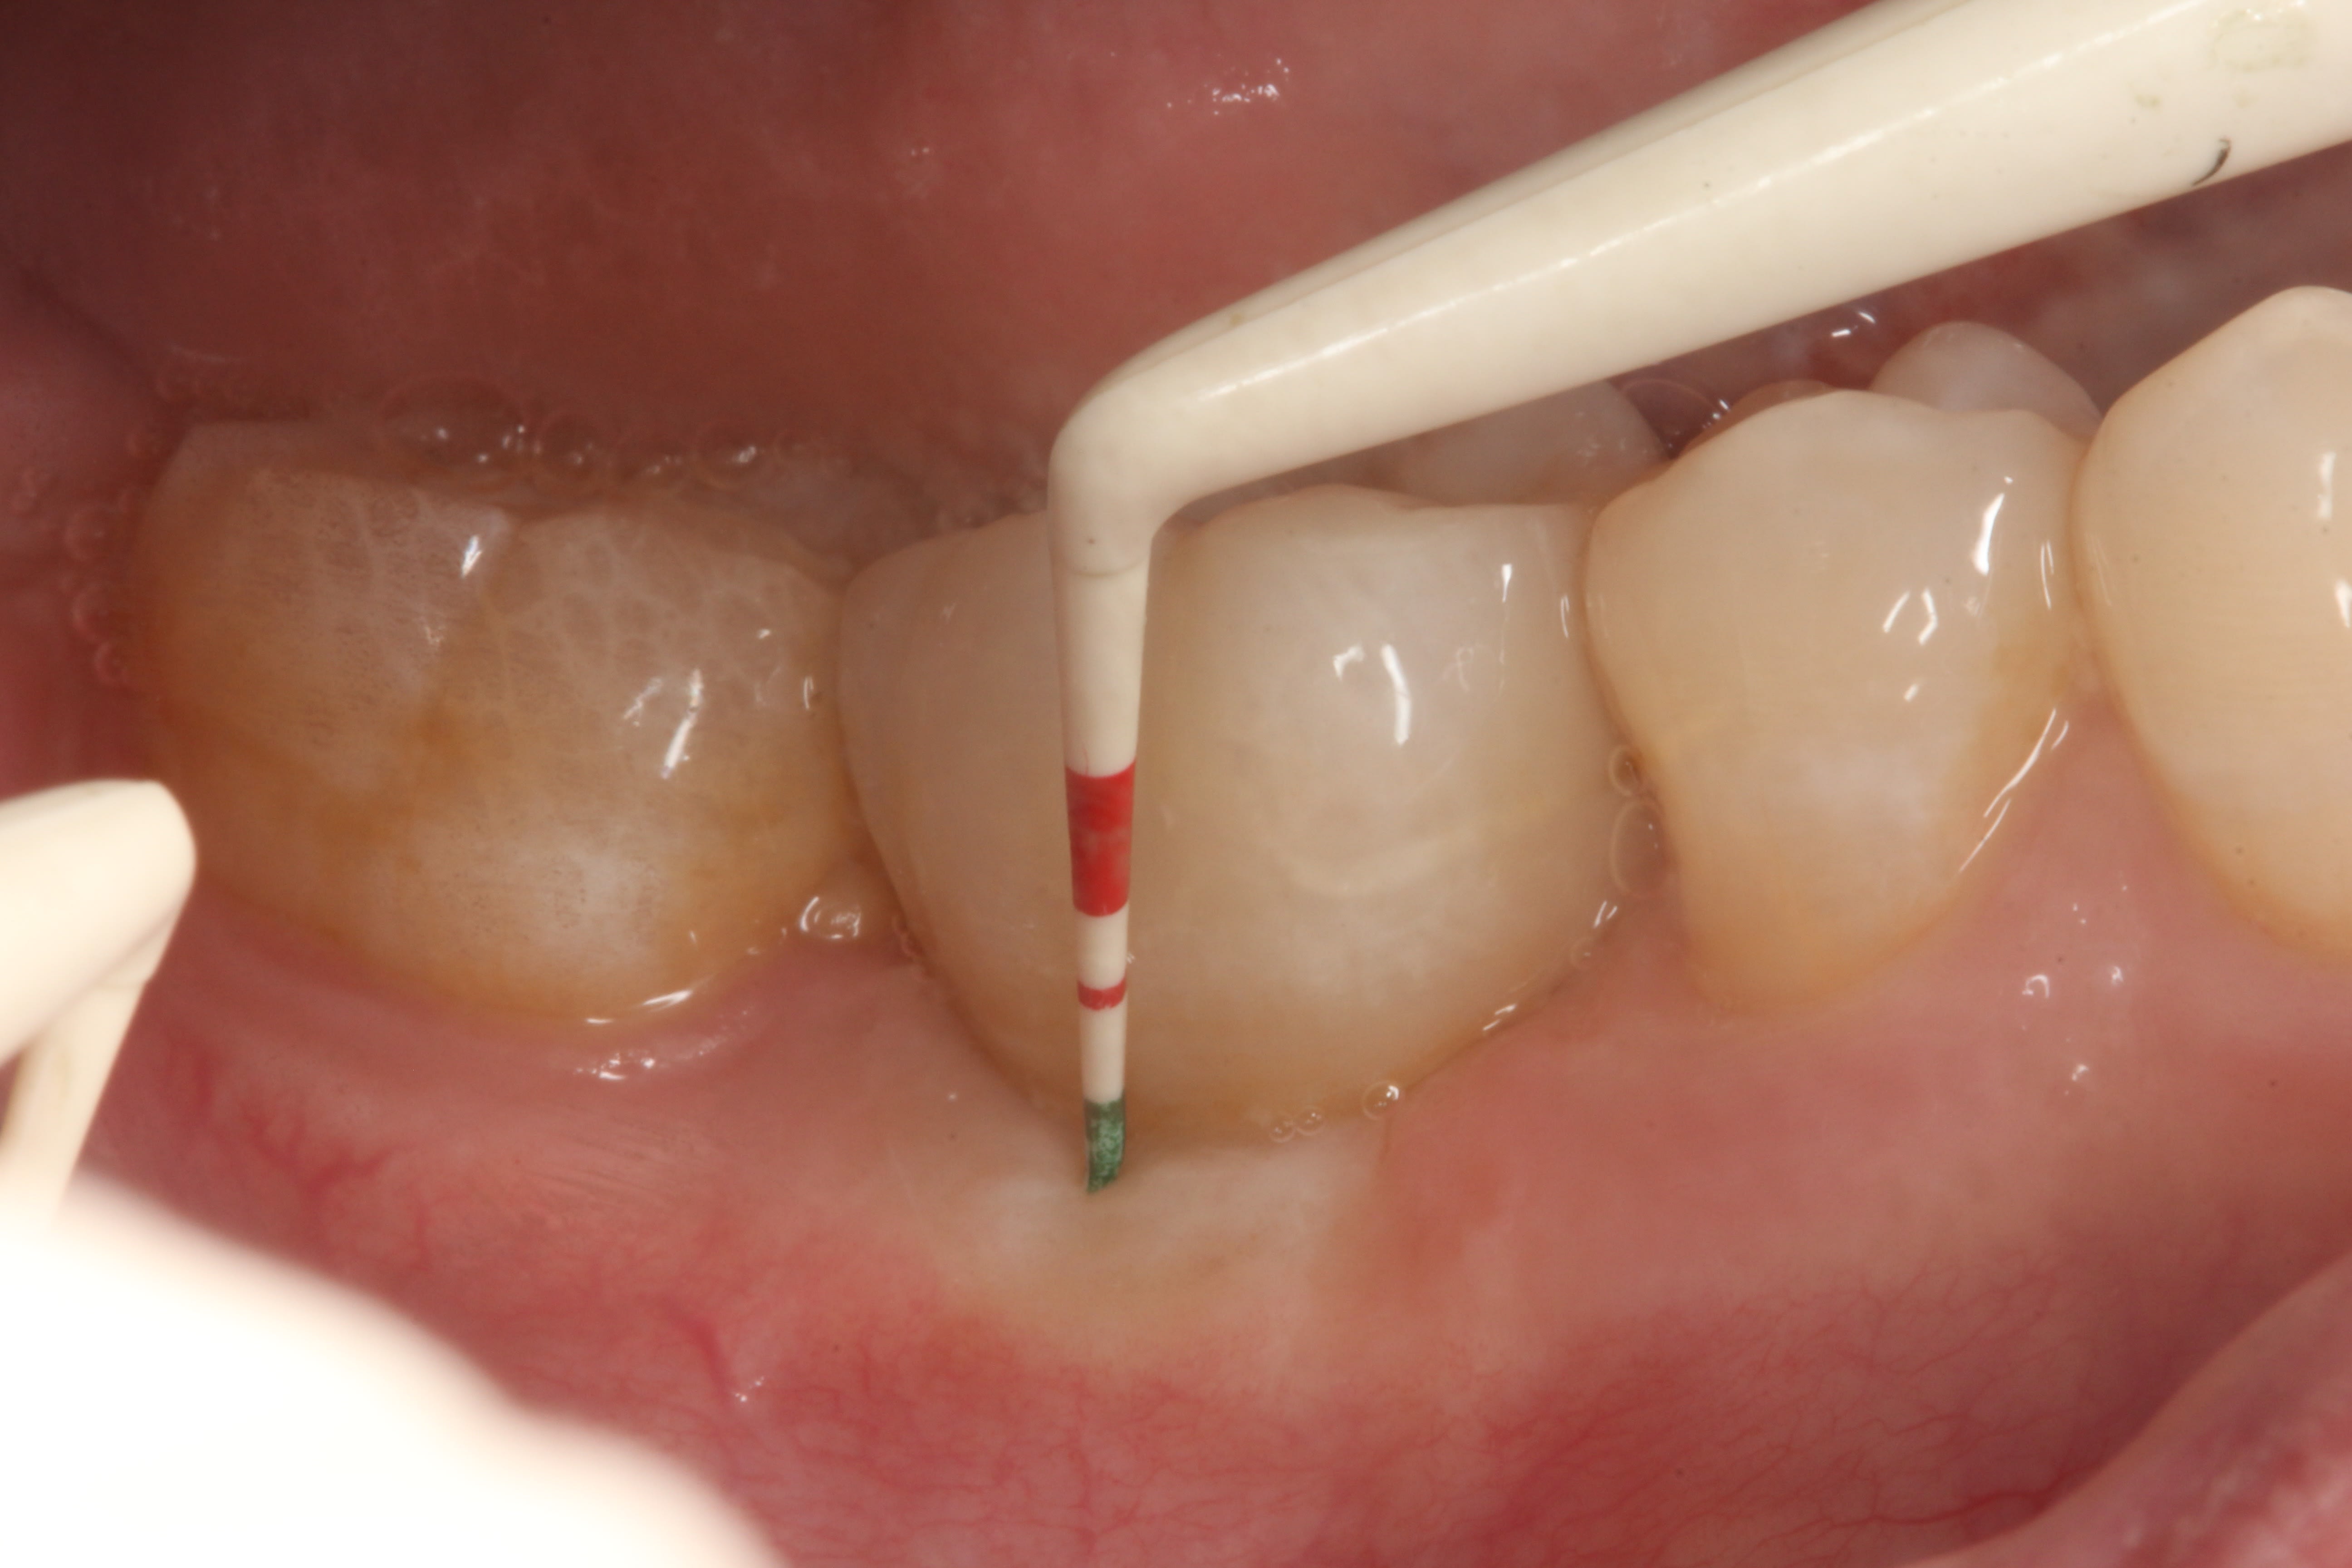

A healthy 69-year-old nonsmoking Caucasian woman presented to one author’s (ALR) periodontal practice with periodontitis involving tooth No. 4. Figure 2 shows a midfacial PD of 3 mm at Visit 1. A PD of 5 mm to 7 mm was present interproximally, with clinical attachment loss of 2 mm to 4 mm; this tooth was also fractured and had a draining sinus tract, and a 7-mm intrabony defect was present on the mesial aspect, suggesting combined periodontic–endodontic involvement (Figure 3). The patient was taking aspirin, trazodone, sertraline, simvastatin, and a calcium supplement (see Table 2 for additional history).

The final impression (closed tray) was obtained in April 2012. The final ceramic crowns (IPS e.max Ceram) and custom porcelain-veneered, regular-diameter (RD) UCLA abutments (Genesis; and Creation CC, Jensen Dental, www.jensendental.com) (Figure 24, shown with PFM crowns and retention screws) were delivered in May 2012. Using a platform-switched connection, the abutments were torqued to 30 Ncm, the access holes sealed with Teflon, and the final crowns cemented with RelyX Unicem. Figure 25 through Figure 28 show the final IPS e.max Ceram crowns from periapical, facial, and incisal views, with a midfacial PD of 3 mm at the 18-month follow-up (Visit 7). A thick biotype is evident in Figure 26, as determined by the inability to detect the outline of the periodontal probe inserted below the restoration’s gingival margin.50 This image also demonstrates an excellent esthetic outcome.